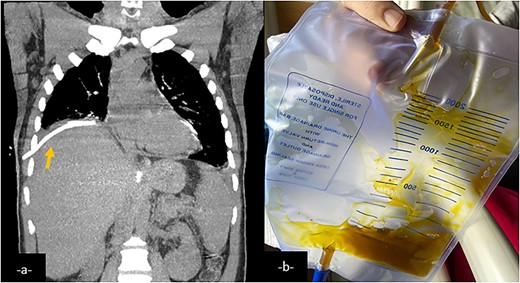

Coronal CT-scan reconstruction after an external drainage of the right pulmonary collection showing a decrease in size of it (a). External drainage finds a brownish fluid consistent with bile (b).

Complete drainage of the pleural, subdiaphragmatic, and perihepatic spaces is the first step in managing BBF. Eliminating any sources of inflammation and irritation, and reducing the pressure gradient responsible of ongoing bile drainage from the biliary tree to the bronchus is essential to ensure the closure of the fistula [12].